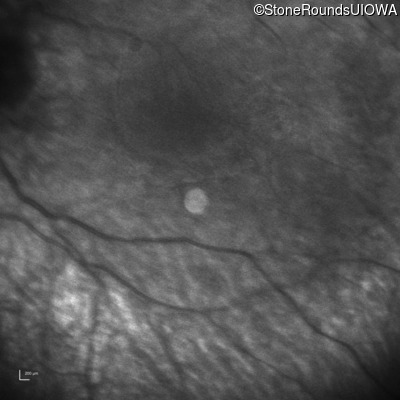

Infrared Fundus Photograph - Right -

No Light Perception

Exemplar

Expanded OCT Stack

×